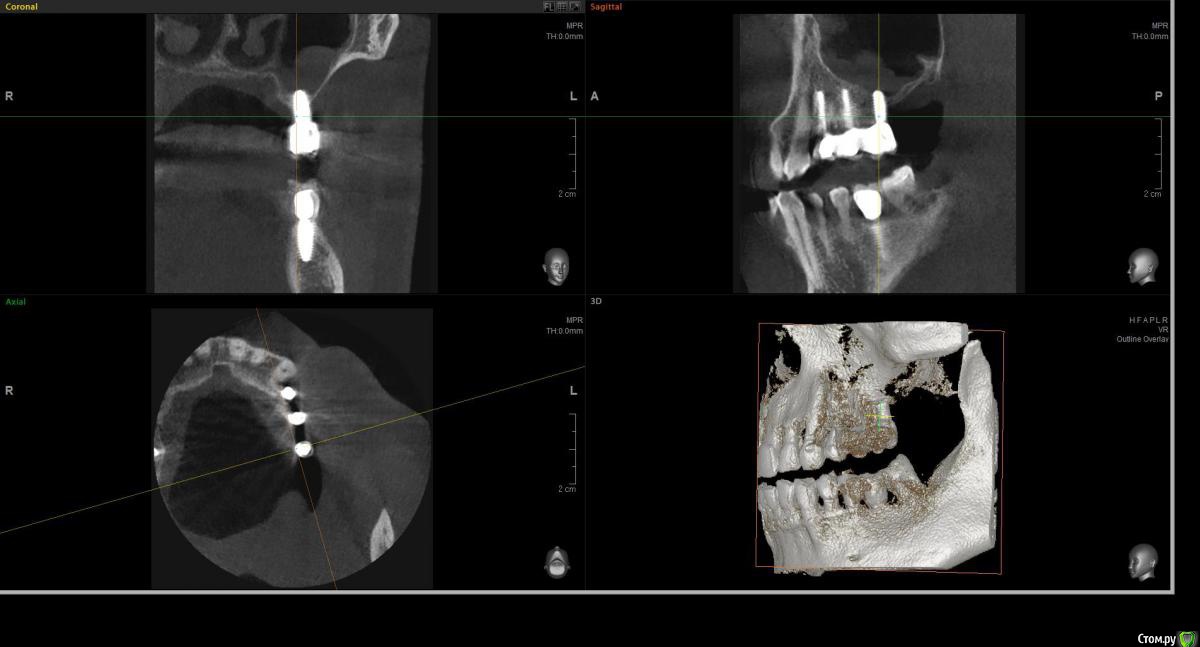

wladdX Опубликовано 20 марта, 2017 Поделиться Опубликовано 20 марта, 2017 (изменено) Несколько скриншотов на скорую руку и снимок из архива, видимо внутриротовая Rg Изменено 20 марта, 2017 пользователем wladdX Ссылка на комментарий

filvik Опубликовано 22 марта, 2017 Автор Поделиться Опубликовано 22 марта, 2017 (изменено) wladdX Спасибо, не знал какие слои выделить.За три года толщина кости уменьшилась где-то на три милиметра.Зубки в коронке стали выше на те-же три милиметра. Изменено 22 марта, 2017 пользователем filvik Ссылка на комментарий

filvik Опубликовано 24 марта, 2017 Автор Поделиться Опубликовано 24 марта, 2017 Как-то, так.К 3-D КТ приложен рентгеновский снимок то, что было в конце в 2013 года, по ниткам резьбыхорошо видна толщина кости в которой сидит дальний имплант (при длине импланта 9 мм.), на КТ 2017 годавидно что с дальней стороны последнего зуба осталось 1,8 милиметра кости.Коронки ставить 1+2 или на каждый отдельно, да и задний имплант похоже держится на честном слове.Вопрос остался прежний что предпринять в данной ситуации? Ссылка на комментарий